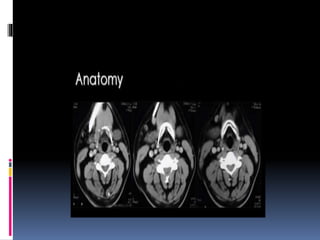

AXIAL SCANS

 Axial scans are best read from inferior to

superior.

 N.L.D., anteroposterior deviations of septum

and nasopharynx can be studied well in Axial cuts

SAGGITAL SECTIONS

 Best for studying details of the lateral nasal wall anatomy